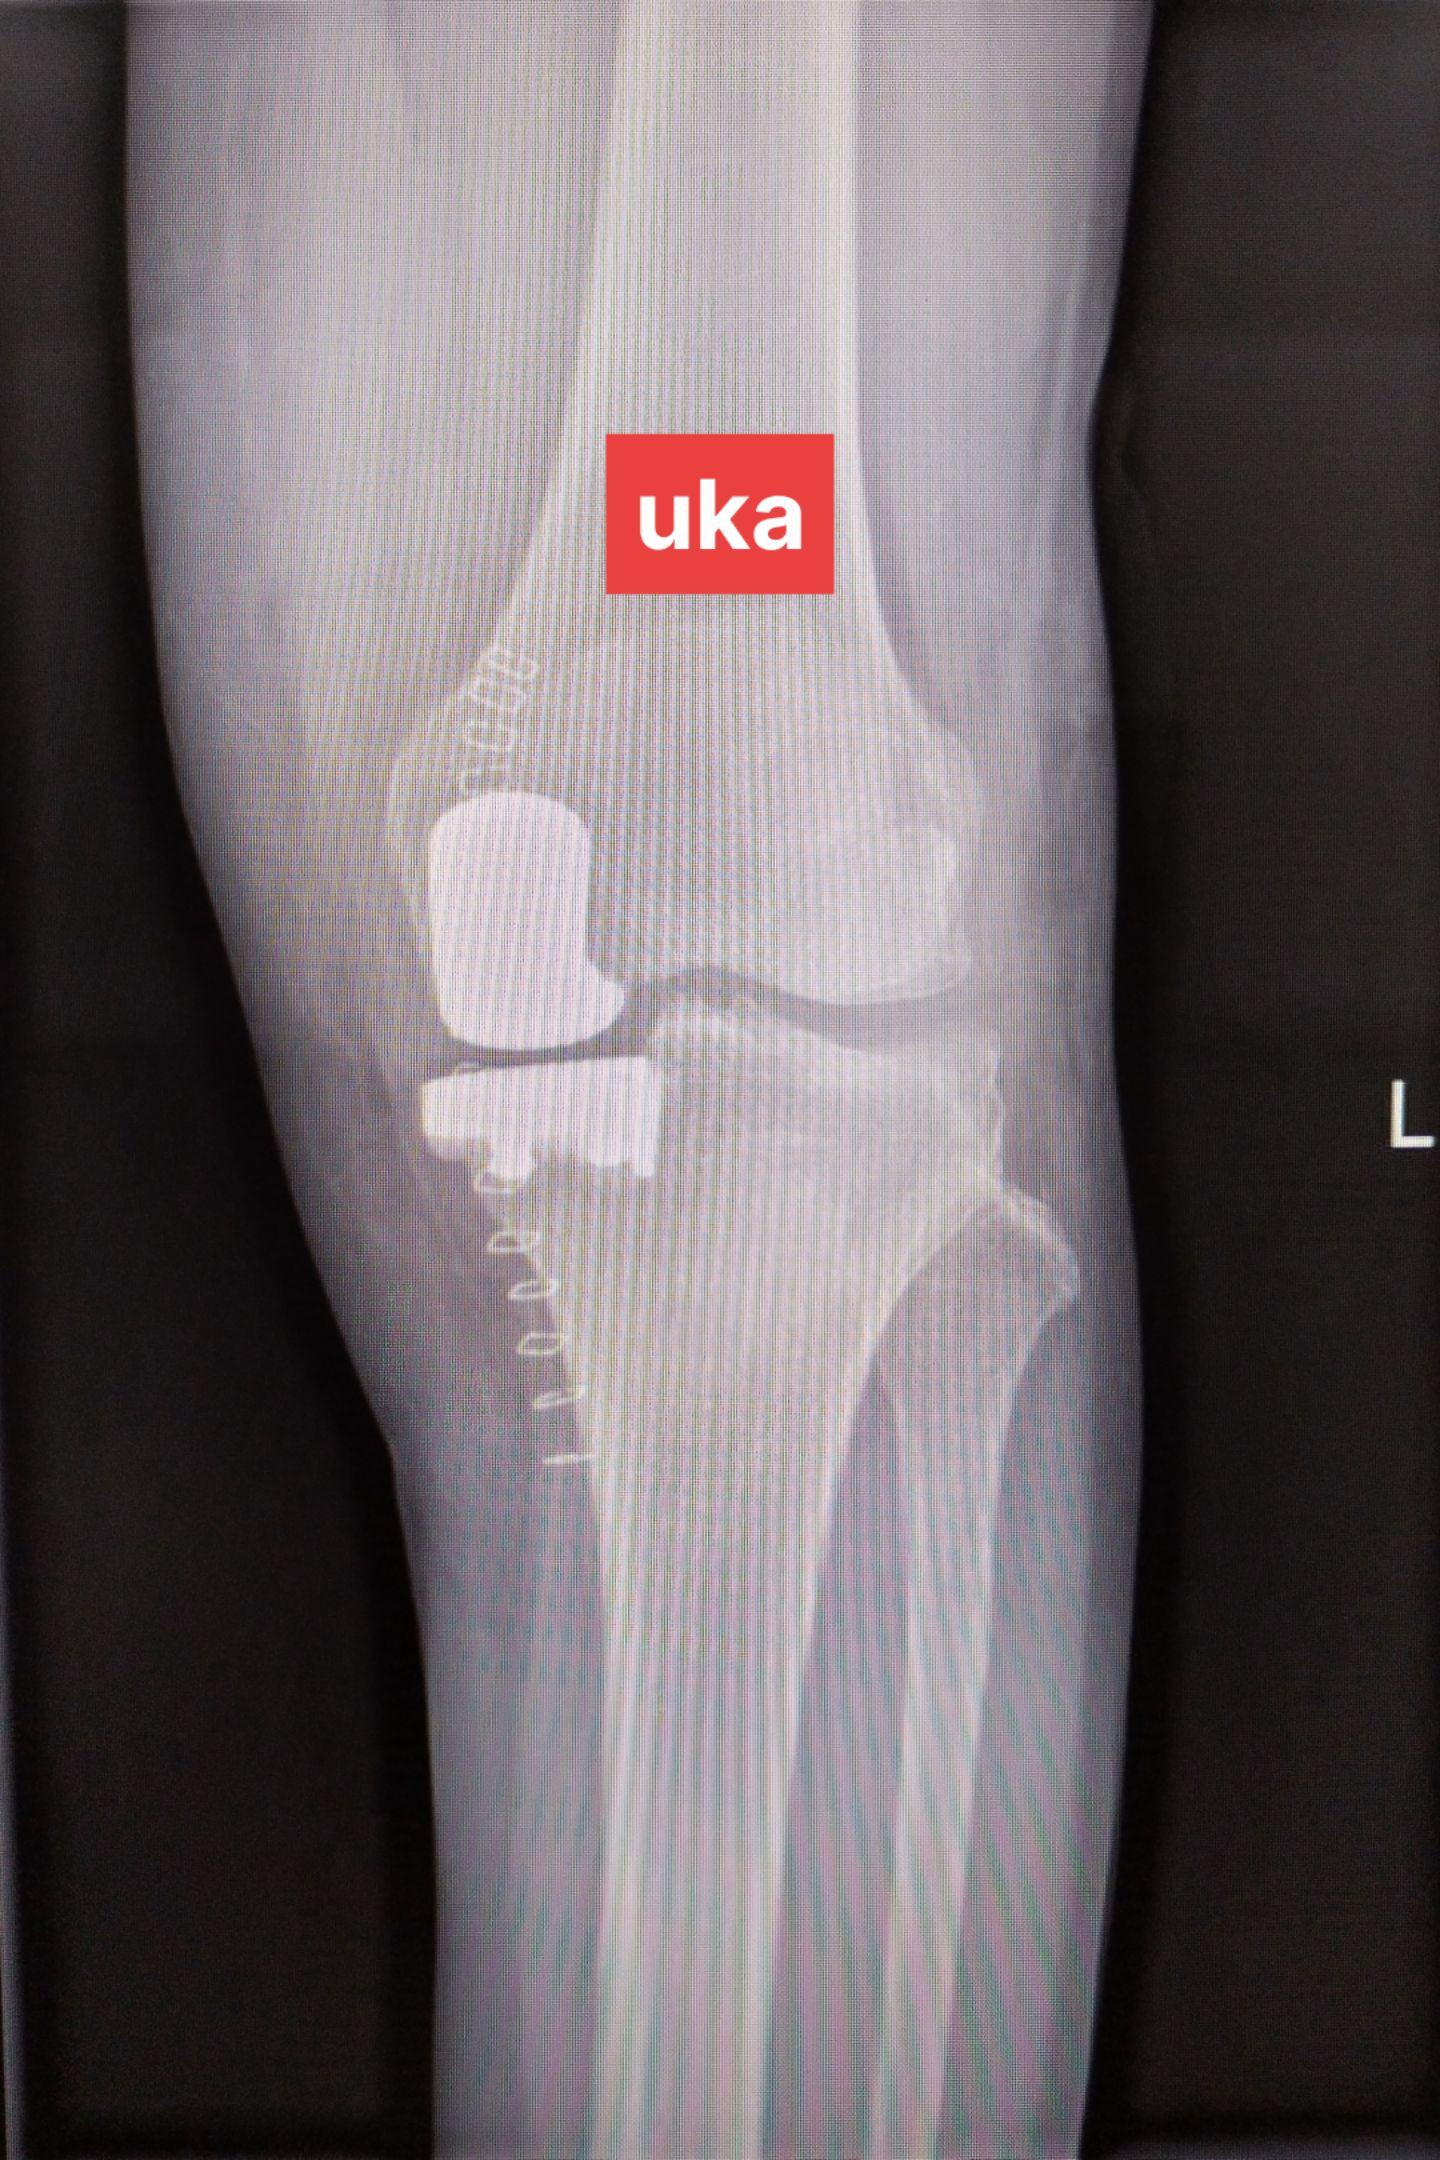

单髁置换术。(看图猜假体)每款假体都有自己的优点,不要单纯追求国产或进口,也不要单纯追求活动平台或固定平台,适合自己才是最好的。愿每一位病人都能快速顺利康复🌹